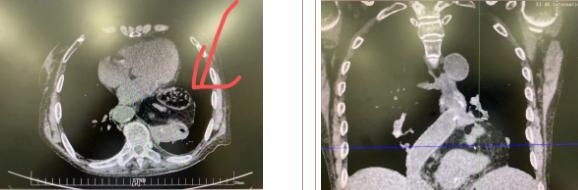

據(jù)了解,患者多年來進(jìn)食后出現(xiàn)惡心、嘔吐,卻未到醫(yī)院進(jìn)行檢查。3個(gè)月前患者突然出現(xiàn)無尿,全身腫脹等情況才前往就醫(yī),卻遭多家醫(yī)院拒收,輾轉(zhuǎn)來到我院就診。檢查發(fā)現(xiàn)患者已患宮頸癌、進(jìn)而引起腎后性腎衰、同時(shí)合并膈疝、出現(xiàn)泌尿道感染,病情及其復(fù)雜。

經(jīng)泌尿外科積極救治,患者腎衰癥狀緩解,隨后轉(zhuǎn)入放射治療中心進(jìn)行宮頸癌根治性放療。放療期間,患者惡心、嘔吐癥狀逐漸加重,后期無法進(jìn)食,排除機(jī)械性腸梗阻和放療因素,考慮因長(zhǎng)期膈疝加重引起,經(jīng)胸外科會(huì)診后轉(zhuǎn)入胸外科一病區(qū)準(zhǔn)備手術(shù)治療。

麻醉手術(shù)中心副主任丁倩為減輕患者術(shù)后不適,實(shí)施單腔聯(lián)合支氣管封堵插管,同時(shí)進(jìn)行了肋間神經(jīng)阻滯麻醉。術(shù)中發(fā)現(xiàn)患者膈疝巨大,食管和疝囊分界不清,部分胃組織和結(jié)腸疝已進(jìn)入胸腔。李文海憑借豐富的臨床經(jīng)驗(yàn),仔細(xì)辨別解剖變異,有序完成分離、縫合、修補(bǔ)等一系列操作,胸外科穆強(qiáng)副主任醫(yī)師、劉歡住院醫(yī)師、麻醉手術(shù)中心團(tuán)隊(duì)通力配合,手術(shù)最終順利完成,患者安全返回胸外科監(jiān)護(hù)室病房。目前患者術(shù)后恢復(fù)良好,于近日準(zhǔn)備出院。